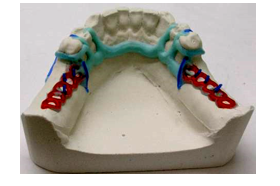

Therapeutic proposals of a typical chassis

* Class I superior

- Main connection : solid plate

- Hooks : 2 Nally Martinet on the 2 teeth bordering the edentulous area

– a mesial occlusal support, this reduces the risk of distal version

– a mesial stem allows free play of the saddle, for axial transmission of forces on the crests independently of the teeth

- 2 retention grids , located in front of the tuberosities.

- Indirect occlusal supports : Indirect cleats, cingulate bar, coronal bar.

* Lower Class I

- Main connection : lingual bar whenever the internal table allows it, otherwise it is a lingual strip.

- Hooks : Nally Martinet on 2 support teeth

- Indirect occlusal supports with a mesial bracket are essential

*Class I mod 1

Treat the embedded edentulism with a fixed prosthesis preferably.

and in 2nd stage: treatment of distal edentulism by metal frame: same outline for class I

Otherwise treat entirely by PPAC: Addition of a saddle previously